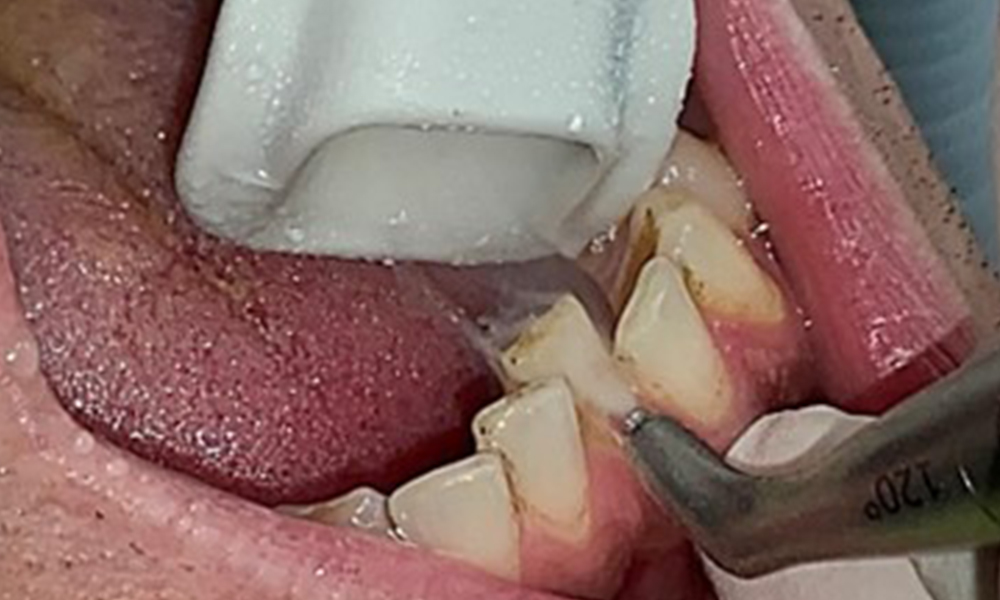

The objective would be to control disease risk by removing supragingival and subgingival biofilm. The instruments can be selected based on patient needs. First, calculus and any concretions must be removed using ultrasonic and/or manual instruments (Fig. 10).

Use of a piezo-driven ultrasonic device in the lingual area near 36 (Proxeo Ultra, W&H, shown here)

Fig. 10 Use of a piezo-driven ultrasonic device in the lingual area near 36 (Proxeo Ultra, W&H, shown here), © Dr R. Krapf